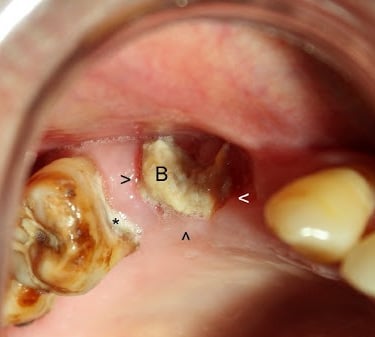

Quiste dentígero

Un quiste dentígero es un saco lleno de líquido que se forma alrededor de la corona de un diente no erupcionado.

Los pacientes pueden notar una hinchazón indolora en la mandíbula.

El tratamiento incluye la extirpación quirúrgica del quiste y, a veces, la extracción del diente involucrado.